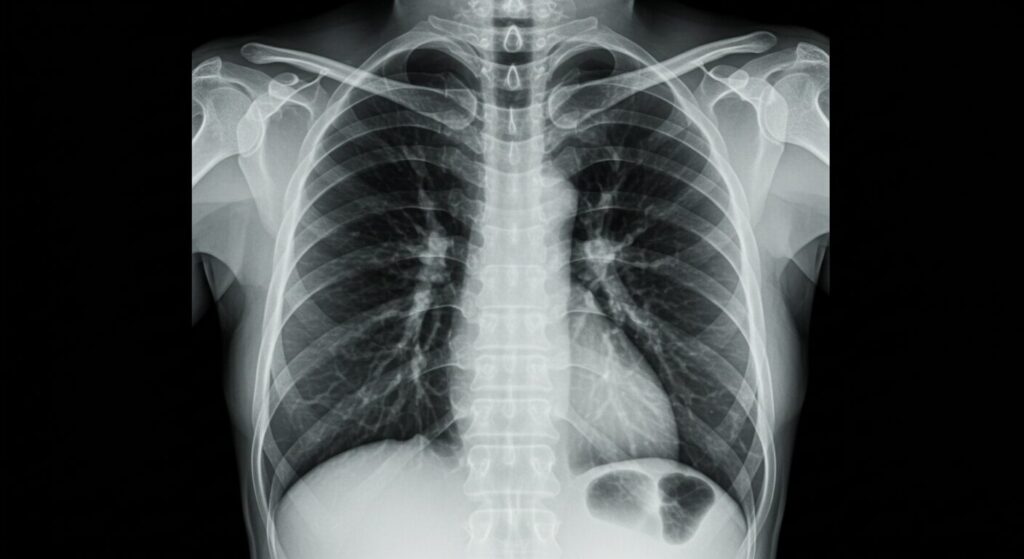

「え、たかが服でしょ?」と思われた方もいらっしゃるかもしれませんね。でも、レントゲン検査はX線という特殊な光を使って体の中を「透かして」見るもの。そこに厚手の服や金属などが重なってしまうと、肝心な部分が影に隠れてしまったり、不自然な影(アーチファクト)ができてしまったりするのです。

レントゲン撮影の基本は、X線が体をどれだけ「透過(すり抜ける)」できるか、にかかっています。密度の高い骨はX線をたくさん吸収するので白く写り、空気で満たされた肺はX線をほとんど吸収しないので黒く写ります。このX線の透過性が、診断画像の明瞭さを決める上でとっても大事なのです 。

まるで、白いカーテン越しに外の景色を眺めるようなものです。カーテンが薄ければ景色はよく見えますが、厚手のカーテンだと、ぼんやりとしか見えませんよね?それと同じで、X線画像上に「白い影」として写り込み、肺の小さな結節や心臓の異常など、本来診断すべき病変がその影に隠れてしまう可能性があるのです。これは、医師が病変を見落とすことにつながり、早期発見のチャンスを逃してしまうことにもなりかねません 。